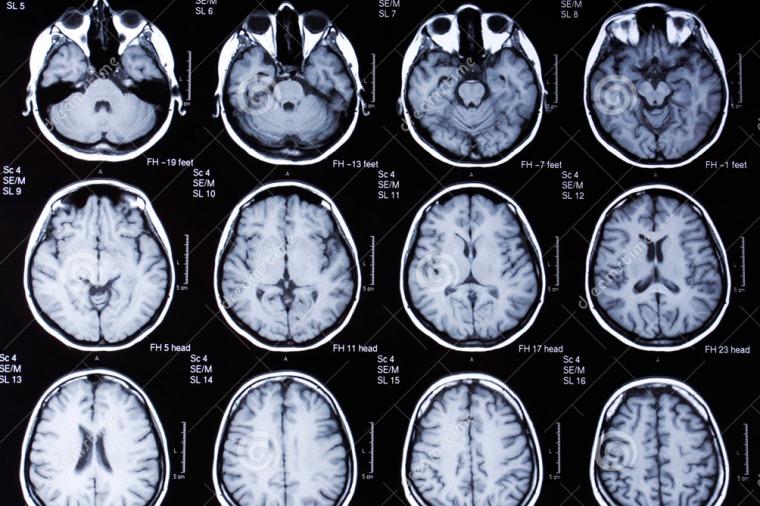

En su investigación se observaron los cerebros de 1.400 personas a través de escáneres MRI (imágenes por resonancia magnética, en sus siglas en inglés) para analizar cuestiones vinculadas al género como el tamaño de algunas regiones cerebrales -distribución de la materia blanca, gris- y la fortaleza de las conexiones neuronales, que son algunas de las principales diferencias entre hombres y mujeres.